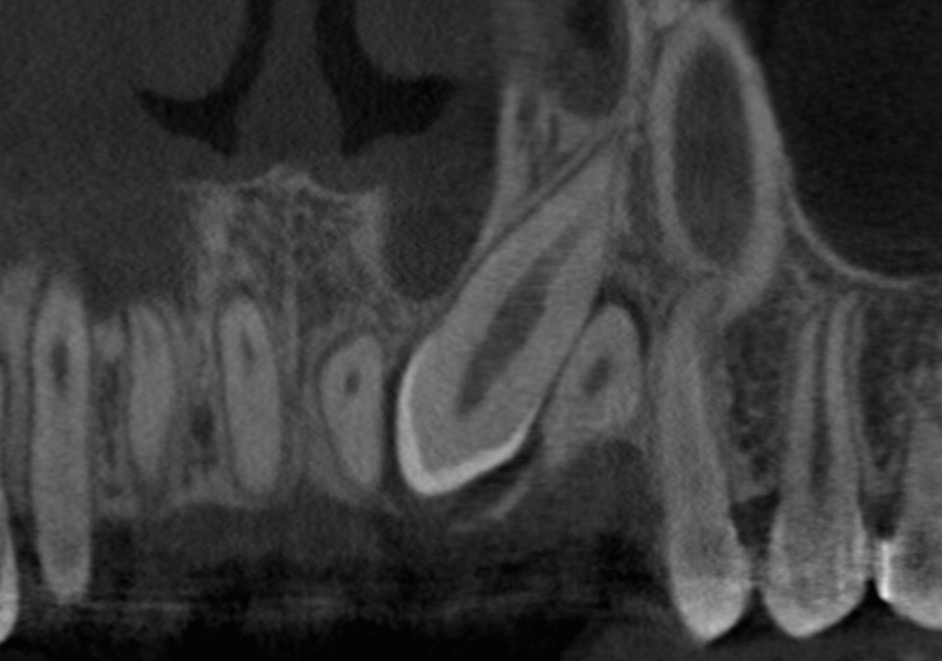

Extraction of Supernumerary Tooth and Exposure of Impacted Lower Lateral Incisor For Orthodontic Eruption

In this video, Dr. H. Ryan Kazemi demonstrates extraction of a supernumerary tooth and exposure technique for orthodontic eruption of impacted tooth #26.addition, he describes the process for immediate placement of a dental implant.